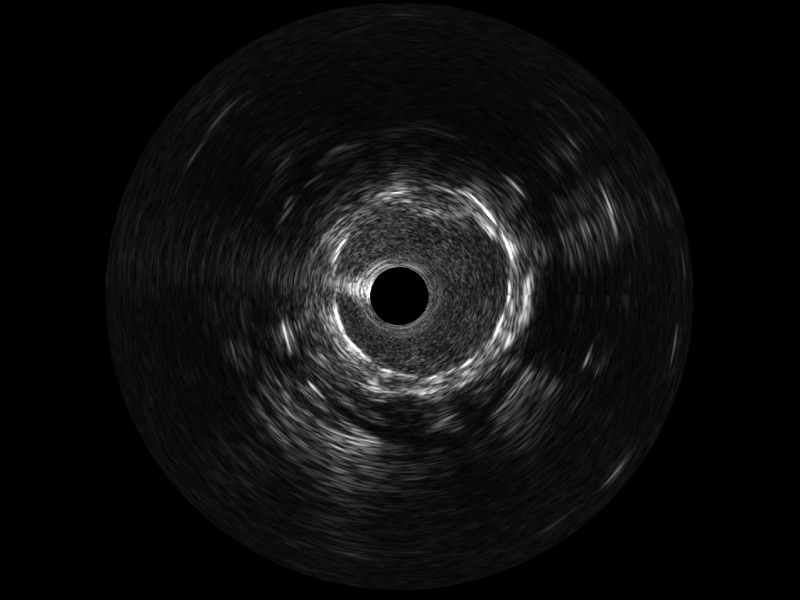

传统IVUS图像

对比传统IVUS导管成像,银河优越会宽频IVUS图像的近场支架梁显影更细腻,远场中膜外血管仍清晰可辨,兼顾远中近,兼顾分辨力与穿透深度